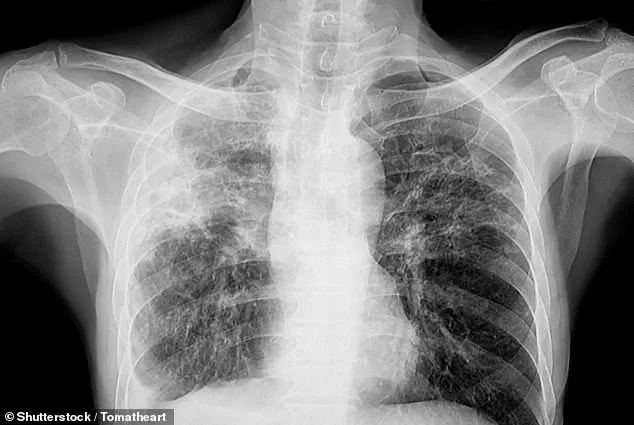

More than 70,000 Britons are currently living with pulmonary fibrosis, a progressive and often fatal condition that scars the lungs, impeding oxygen exchange and causing debilitating shortness of breath.

The disease, which can be triggered by exposure to asbestos, occupational dust, or even certain medications, is typically associated with respiratory symptoms.